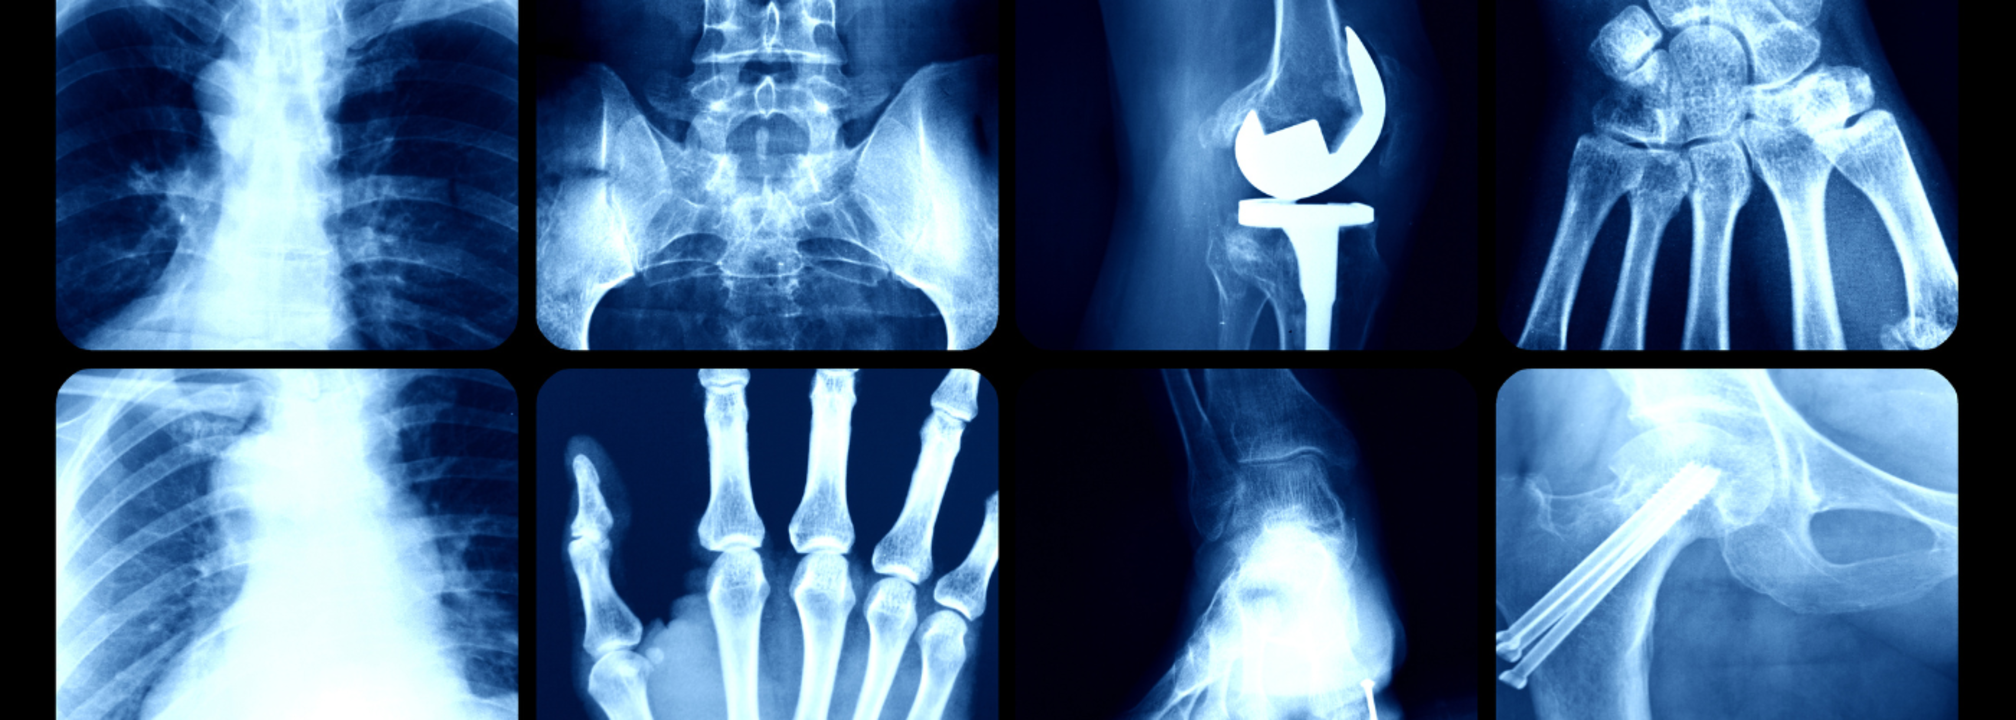

Of the many things new, a groundbreaking mobile X-ray service in Devon saved up to 700 hospital beds in three months. This was all possible due to the game changer, mobile X-ray. The service was being trialled at the Derriford Hospital in Plymouth, where patients received X-ray examinations in their own homes, this reduced the need for hospital visits, especially to the vulnerable and elderly patients. This also freed up ambulances and improved overall patient care. How does it make a difference?It was originally used in the hospitals itself, with mobile X-ray units being set up within the hospitals for patients under intensive care, who could not be transported to radiology departments. Now, the service has expanded to nursing homes and also to private residences. This is especially beneficial to the frail, elderly or disabled patients who may struggle to visit hospitals.The BBC reports, Sheila, a 90-year-old care home resident in Devon also benefited from the service after a fall. Instead of an ambulance trip to the hospital, the mobile X-ray team arrived the same day and confirmed a fracture. It also arranged for the appropriate treatment. "It was amazing," said her home manager Diane Kehoe. "It is so fast and has made a huge difference."How Was It Introduced?It was in 2024, when around 2,000 patients over the age of 55 visited Derriford's Emergency Department, only to be told that they had not suffered a fracture Of these, around 1,300 arrived via ambulance, and 1,000 were admitted unnecessarily. Mobile X-rays, thus reduce these numbers and provide comfort to patients in a familiar surrounding, which is within their houses.The University Hospitals Plymouth NHS Trust has received overwhelmingly positive feedback from care homes and patients. The service was initially piloted in Cornwall and is now running in Devon for a 12-month trial.How Does It Work?Mobile X-ray services bring imaging technology to patients at home. It also ensures of a quick and precise imaging. It uses digital radiography that captures high resolution images for an accurate diagnosis. Furthermore, it also follows strict ALARA, which stands for As Low As Reasonably Achievable principles to minimize the radiation exposure, The person who receives the imaging at home is at a greater benefit, especially if the patient is vulnerable to diseases, as they can avoid hospital-acquired infections. These images are also transferred to physicians with reports available within 24 hours. It is capable of diagnosing orthopedic injuries, including fractures, dislocation and bone deformities. It can also diagnose lung conditions like pneumonia, pleural effusion and lung fibrosis; spinal disorders like scoliosis, degenerative disc disease, and abdominal issues like bowel obstruction, kidney stones, and foreign objects. The procedure usually takes around 10 to 15 minutes and the results too are quickly processed. The best thing is that mobile X-rays also follow pediatric protocols, ensuring safe imaging for children.While mobile radiography offers clear benefits, such as faster diagnosis, less hospital load, and greater patient comfort, it also has certain disadvantages. These include physical demands on radiographers, logistical planning, and acquiring the necessary approvals. However, the overwhelming positive impact on patients, particularly those with dementia or mobility issues, qualifies it as a significant medical breakthrough.